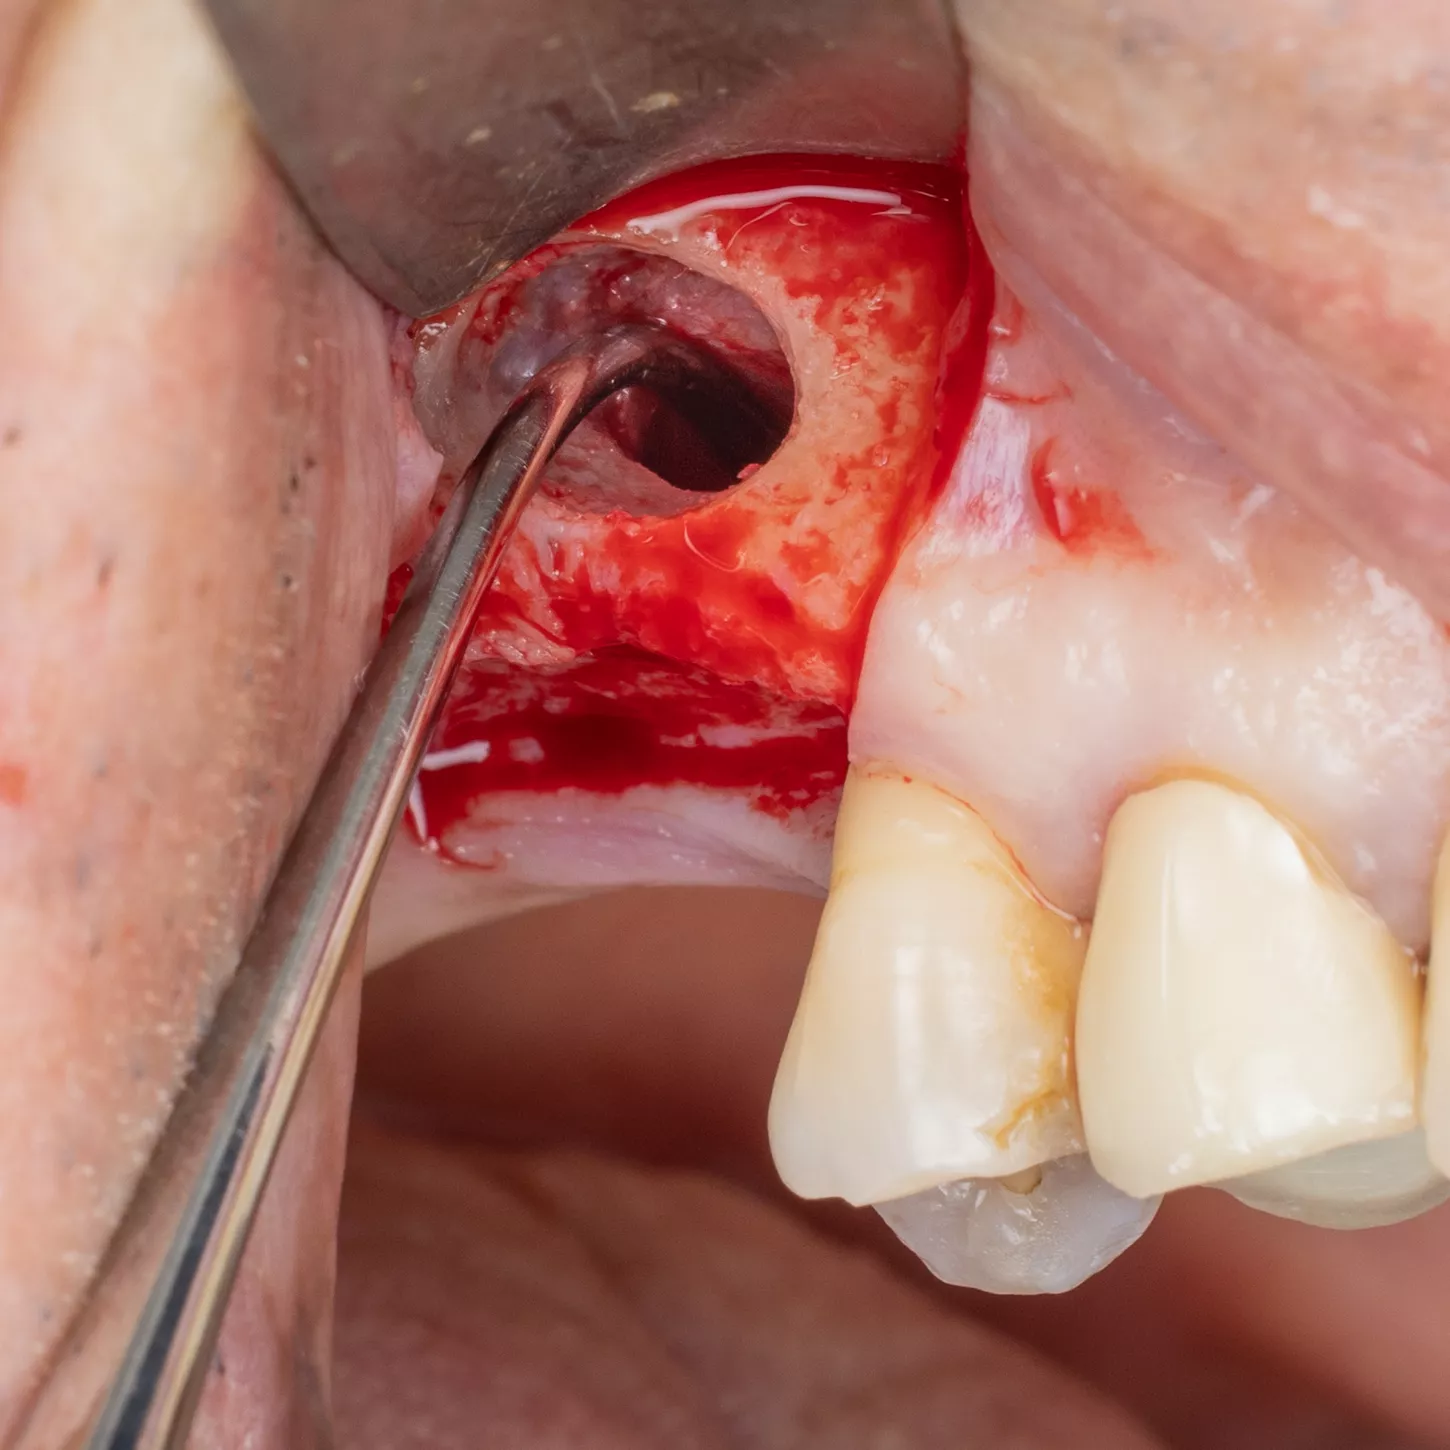

14. The last drill used has a Ø 3.0 mm diameter (red), for the placement of Axiom® BL X3 Ø 4.0 mm and 10mm length implant and confirmation of the axis using the adapted gauge.

16. Prior to implant placement, filling of the palatal and mesial area of the sinus cavity with axenogenic biomaterial (XenoGraft, Straumann®).

17. Filling and compression using a graft packer in the mesio-palatal direction.

18. The sinus cavity is densely packed with the bone graft composite to support the implant.